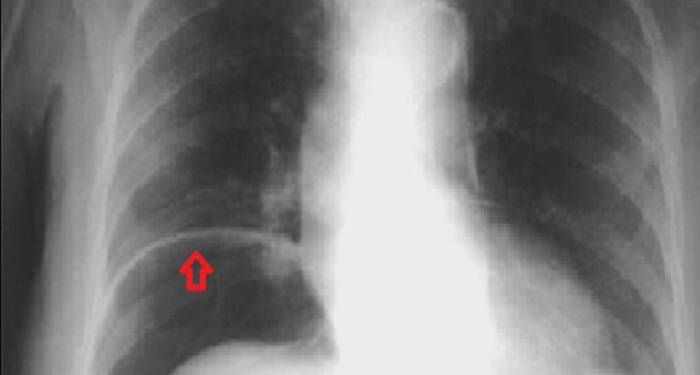

Ο ασθενής εισήχθη στο νοσοκομείο της Κλαϊπέντα, στη Βαλτική, καθώς παραπονιόταν για οξείς πόνους στην κοιλιακή χώρα. Οι γιατροί του έκαναν ακτινογραφία και σύντομα ανακάλυψαν πως μέσα στο στομάχι του υπήρχαν διάφορα μεταλλικά αντικείμενα, ορισμένα εκ των οποίων είχαν μήκος έως και 10 εκατοστά, με αποτέλεσμα να κινδυνεύει η ζωή του.

«Κατά τη διάρκεια της επέμβασης διάρκειας 3 ωρών (…), όλα τα ξένα σώματα, ακόμα και τα μικρότερα, αφαιρέθηκαν από το στομάχι του ασθενούς», δήλωσε ο χειρουργός Σαρούνας Νταϊλιντένας. Το νοσοκομείο έδωσε στη δημοσιότητα μια φωτογραφία από τις βίδες και τα καρφιά που βρέθηκαν στο στομάχι του ασθενούς.